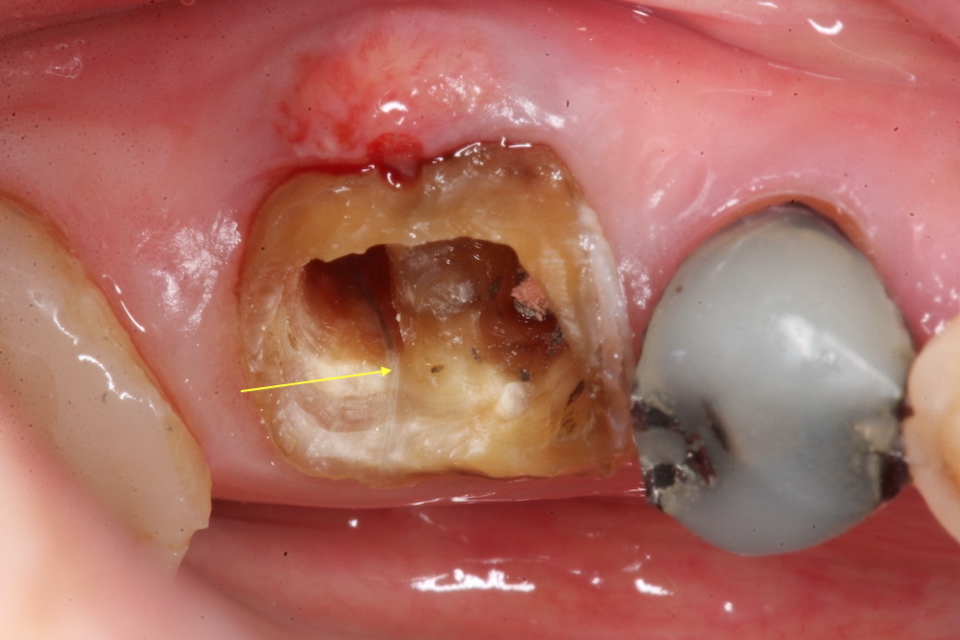

今日の抜歯再植術シリーズ39.1 2025.11.14